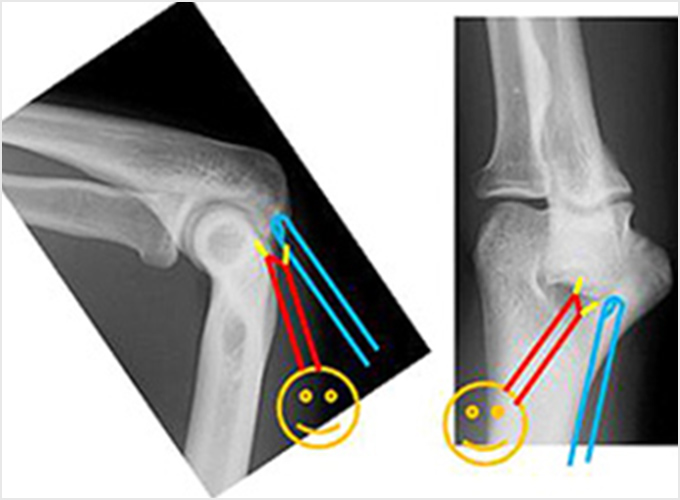

同様にボールを投げ肘が伸びるとき(フォロースルー)に、肘の後ろで骨同士の衝突が起こり、これを繰り返すことで疲労骨折が起こることがあります(図6a)。骨端線が癒合した中学~高校以降で起こります。投球を休止し、フォームや体の硬さなどの問題を改善し、再発を予防します。なかなか治らない場合、繰り返す場合にはボルトなどで疲労骨折を固定する手術を行うことがあります(図6b)。

肘頭骨棘骨折

投球を繰り返すことで少しずつ骨に棘(とげ)のような余分な骨ができてくることがあります。これを骨棘(こつきょく)といいます(図7a)。投球で肘が伸びたときに、肘の後ろで骨同士の衝突が起こり、骨棘が骨折します。投球を休止し、フォームや体の硬さなどの問題を改善したりして、再発を予防します。なかなか治らない、繰り返すなどの場合には関節鏡を用いて骨のかけらや骨棘を切除する手術を行います(図7b.c)。